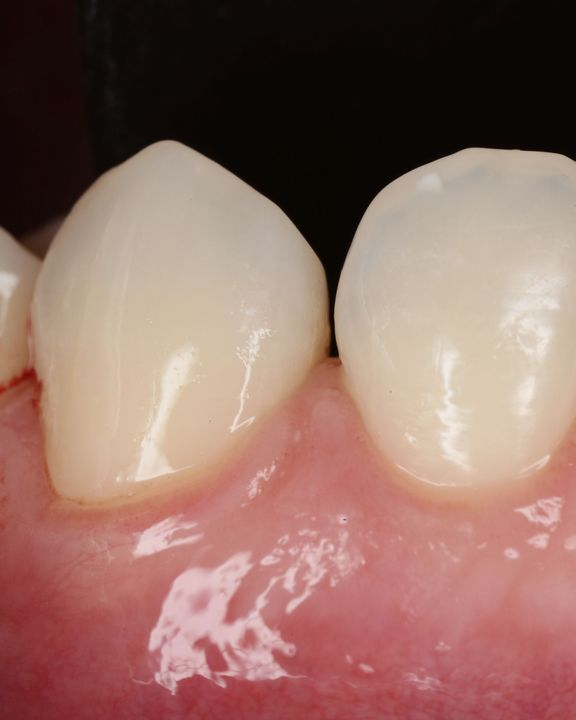

La microchirurgia plastica parodontale è utilizzata per arrestare la progressione di malattie parodontali e delle recessioni gengivali (retrazione delle gengive), ma anche per migliorare l’aspetto estetico della linea gengivale e del sorriso.

Radici dentali esposte sono il risultato della recessione gengivale. I denti in questi casi spesso sono sensibili a cibi e liquidi caldi, freddi o acidi. Le cause per cui si hanno recessioni gengivali sono le stessa da cui originano le parodontiti, prime tra tutte placca batterica, scarsa igiene orale, traumatismi, fumo. Esistono poi una varietà di fattori predisponenti che dovrebbero essere individuati per limitarne l’azione distruttiva e per prevenire l’ulteriore perdita di gengiva ed osso.

Innesti di tessuto molle possono essere utilizzati per coprire le radici esposte ma anche per ricostruire il tessuto che è andato perso. Il tessuto molle viene prelevato dal palato o da altre zone intraorali. L’intervento è quasi indolore e non esistono possibilità di rigetti. Il tessuto prelevato dalla zona donatrice si riforma spontaneamente in poche settimane.

Numerosi benefici derivano dalla chirurgia plastica parodontale: l’innesto di tessuto molle ricostruisce il tessuto perso e previene l’ulteriore progressione della recessione gengivale e dell’osso alveolare. Gli innesti gengivali riducono la sensibilità del dente e prevengono la formazione delle carie alle radici. E soprattutto migliorano l’aspetto estetico della linea gengivale e quindi del sorriso di ogni paziente.